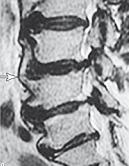

![]() На рентгенограмме № 4 изображен межпозвонковый сегмент в далеко зашедшей стадии дегенерации. Спондилёз второй степени в сочетании со снижением межпозвонкового промежутка говорит о том, что в прошлом на данном уровне имелась протрузия межпозвонкового диска, которая была стабилизирована развившейся стадией фибротизации поражённого диска (что хорошо видно на МРТ № 37). Бывает, что спондилёз может травмировать эпидуральную клетчатку (при движении позвоночника), в результате чего в ней возникают асептические воспалительные процессы. Эпидуральная клетчатка со временем уплотняется, склерозируется, в ней появляются фиброзные тяжи, которые могут деформировать спинномозговой корешок, вызвать его натяжение или сдавление. А при значительном увеличении (разрастании) спондилёза может развиться стеноз спинномозгового канала второго типа (первый тип стеноза — врождённый, второй — приобретённый), что довольно часто бывает при срыве адаптивных механизмов во время развития дегенеративно-дистрофических процессов в межпозвонковых дисках. Рентгенограмма № 5 ![]() МРТ № 38 ![]() На рентгенограмме № 5 шейного отдела позвоночника — выраженный спондилёз третьей степени и остеофитоз, что хорошо видно на МРТ № 38 сегментов шейного отдела позвоночника. В целом можно сказать, несмотря на то что спондилёз и остеофиты являются следствием определённых заболеваний позвоночника и в некоторой степени способствуют биомеханическим нарушениям в других сегментах позвоночника, всё же они небесполезны. Во многих случаях это своеобразная «скорая помощь» организма в ответ на невозможность осуществить полноценную регенерацию повреждённого позвоночно-двигательного сегмента. Данные костные наросты хоть и ограничивают движение сегмента, но тем самым предупреждают и замедляют его дальнейшее разрушение. Так что если при обследовании позвоночника у вас обнаружат спондилёз или остеофиты, то не стоит бояться этого диагноза. На самом деле всё не так страшно, как кажется на первый взгляд. Рентгенограмма № 6 ![]() МРТ № 39

На рентгенограмме № 6 поясничного отдела позвоночника выраженный остеофитоз, спондилёз третьей степени, что также хорошо видно на МРТ № 39 поясничного отдела позвоночника МРТ № 40 ![]() МРТ № 41